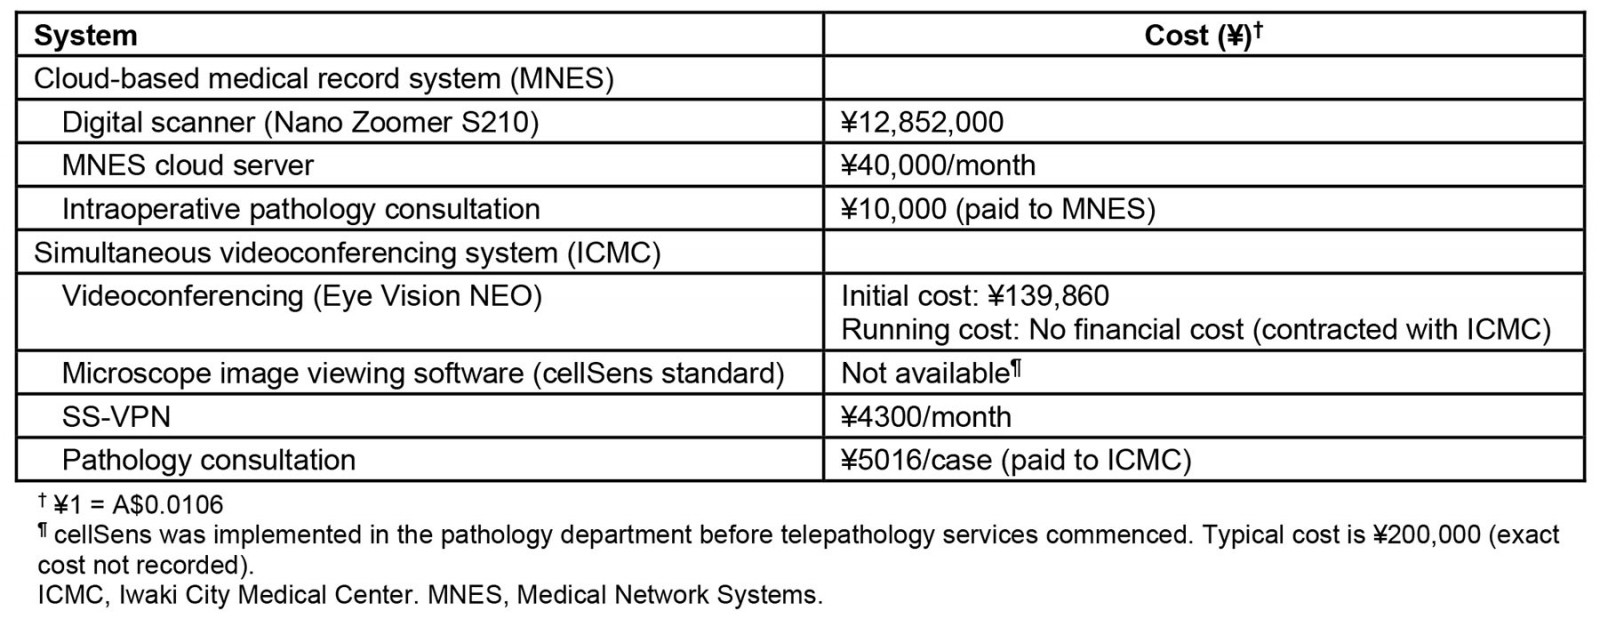

We identified 45 patients within the study period and all of them were included in the further analysis (median age 67 years, interquartile range 48–77, all female; Table 2). Only one patient (2%) received neoadjuvant chemotherapy before surgery, while 23 (51%) received mastectomy and 22 (49%) received breast conservative surgery.

Table 2: Clinical characteristics of patients (n=45)